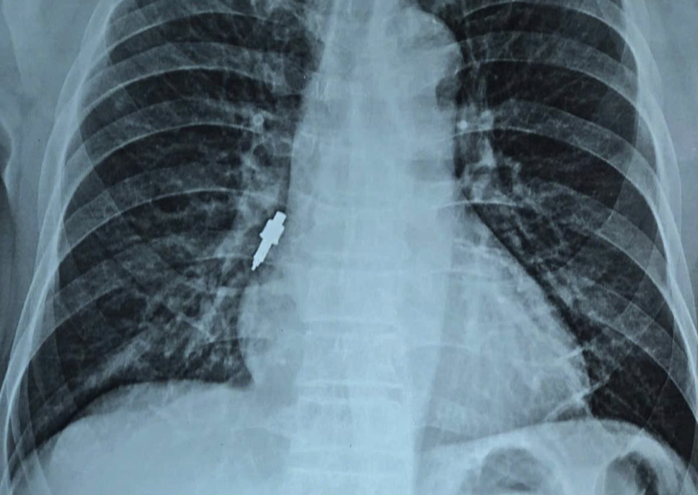

Dị vật phát hiện nằm trong phế quản phải. Ảnh: Bác sĩ cung cấp

Sau đó, bệnh nhân xuất hiện ho nhẹ đến kéo dài. Cách một ngày trước khi nhập viện, bệnh nhân ho tăng nhiều, chụp X-quang phát hiện vật cản ở phế quản phải nên được đưa đến bệnh viện.

Bác sĩ xác định đây là trường hợp dị vật đường thở hiếm gặp. Bệnh nhân được nội soi phế quản cấp cứu. Quá trình lấy dị vật gặp nhiều khó khăn vì vật thể bằng inox, trơn, kích thước lớn, dài 2,5 cm, đường kính chỗ rộng nhất khoảng 1 cm và mắc sâu vào phế quản phải.